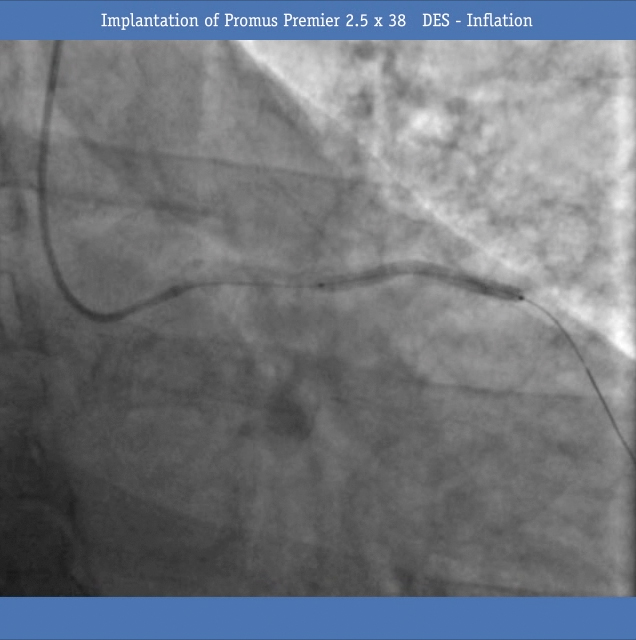

• Next, a Promus Premier 2.5 x38 DES was implanted (Figure 4) and inflated (Figure 5) and post dilated with a non-compliant balloon 2.5x20 mm